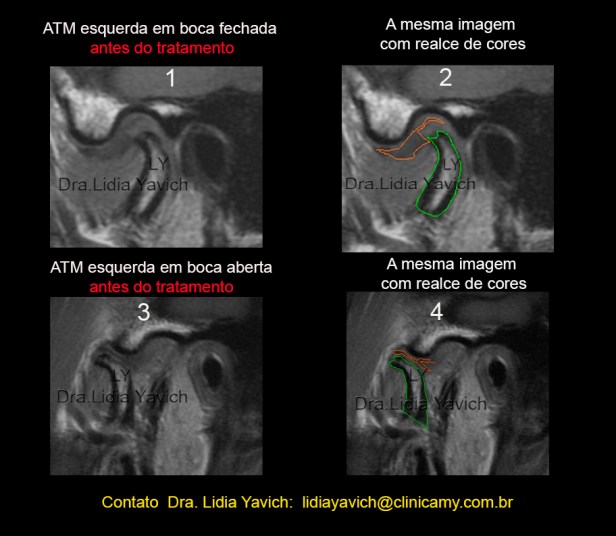

RNM: Ressonância Nuclear Magnética do paciente. Corte selecionado.

1 corte sagital da ATM ESQUERDA em boca fechada antes do tratamento. Deslocamento redutivel do disco articular.

2 -A mesma imagem com realce de cores.

3 -corte sagital da ATM ESQUERDA em boca aberta antes do tratamento.

4– A mesma imagem com realce de cores.  RNM: Ressonância Nuclear Magnética do paciente. Corte selecionado. Corte sagital da ATM DIREITA em boca fechada antes do tratamento.